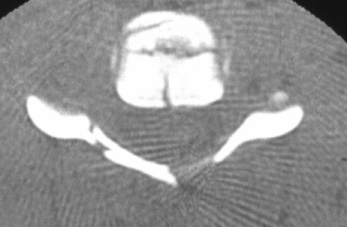

Compresie bilaterala Aspect CT Disjunctie sacro-iliaca stanga Compresie antero-posterioara

Cistograma Fracturi ale ambelor

ramuri pubiene

Contur neregulat al vezicii urinare Disjunctie

sacro-iliaca dreapta